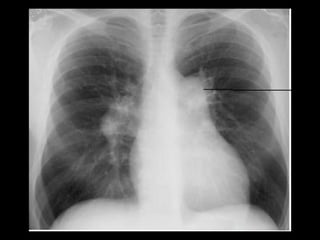

Exames de imagem: Rx Tórax

Primeiro passo na investigação radiológica da

suspeita de HAP;

Achados típicos: aumento do calibre das artérias

centrais, com rápido afilamento dos vasos à medida

que progridem para a periferia;

A área cardíaca pode estar aumentada ou normal;

Calcificação vascular: associado a alta RVP;

Sensibilidade baixa;

Útil para afastar ou sugerir causas de HAP;

Radiografia de tórax normal

HAPI: imagem: Rx e TC

Aumento do calibre dos vasos pulmonares;

Afilamento dos vasos e oligoemia;

Sinais de cardiomegalia direita;

Tortuosidade dos vasos pulmonares periféricos;

Em alguns pacientes: nódulos centrolobulares em

vidro fosco(hemorragia, congestão vascular ou

depósitos de colesterol);

Padrão em mosaico: em alguns pacientes;